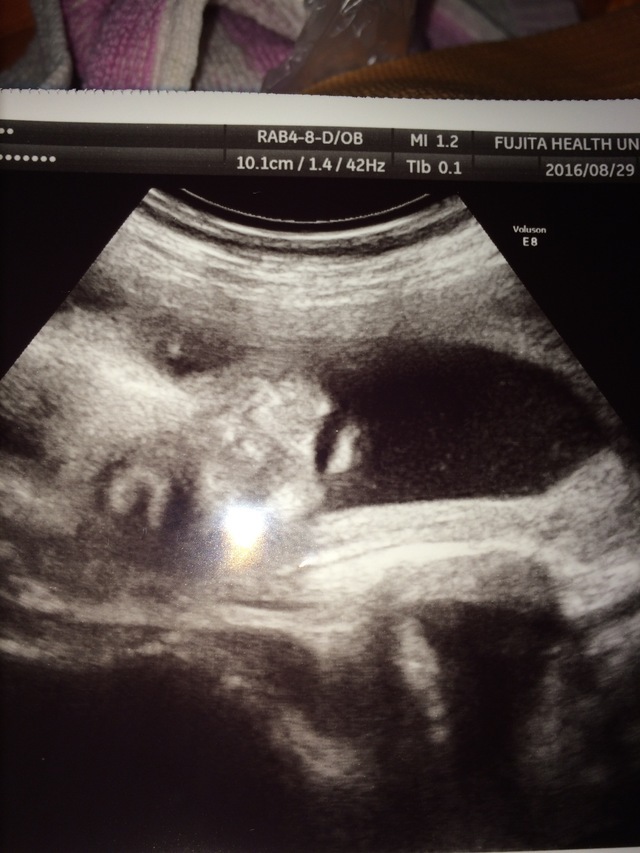

26週6日(26w6d・男の子)|もんちゃん623 さん(31歳)

エコー写真撮影時のエピソード:

2Dエコーなのですが、お顔がはっきり見えて旦那さんにそっくりだったので、とてもお気に入りです。

鼻がちょっとぺちゃっとなってるところが、またさらに可愛くてとても愛おしいです。

これから、大きくなってさらにお顔がわかってくるのがとても楽しみになりました。